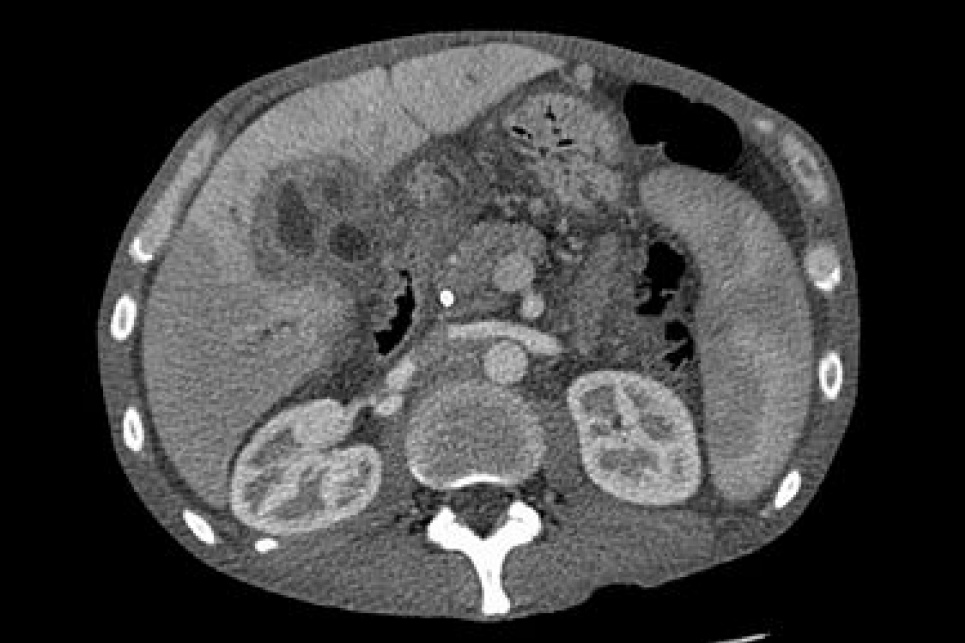

Гепатоцелюлярна карциномаМОЗ наказом від 26.01.2024 № 143 затвердило Стандарт медичної допомоги при гепатоцелюлярній карциномі. Про це пише "Медична справа".

Гепатоцелюлярна карцинома — це одна з тих локалізацій злоякісних пухлин, які важко діагностуються на ранніх стадіях з причини безсимптомності перебігу та через повільні, незворотні зміни, які відбуваються в організмі внаслідок росту пухлини.